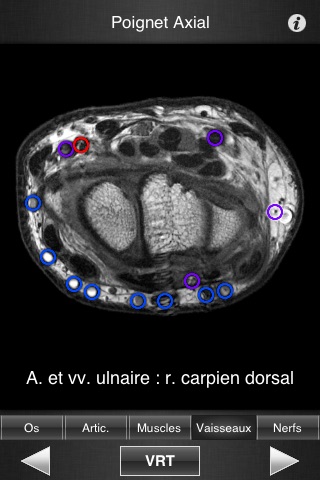

Il contient 502 coupes d’IRM jointives (2-4 mm dépaisseur) dans les trois plans de l’espace.

- Plus de 500 légendes différentes, fidèles à Terminologia Anatomica et à la littérature récente.

- Plus de 16 000 repères anatomiques définis.

- Lecture des légendes facilitée grâce à une segmentation en cinq modes (os, articulation, muscles, vaisseaux, nerfs)

- Images de haute qualité avec fonction de zoom